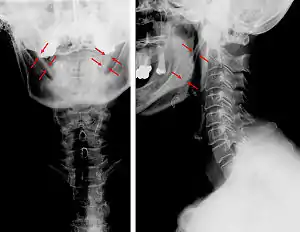

| Anteroposterior and lateral radiographs of cervical spine showing ossification of the stylohyoid ligament on both sides | |

Eagle syndrome (also termed stylohyoid syndrome,[1] styloid syndrome,[2] styloid-stylohyoid syndrome,[2] or styloid–carotid artery syndrome)[3] is a rare condition commonly characterized but not limited to sudden, sharp nerve-like pain in the jaw bone and joint, back of the throat, and base of the tongue, triggered by swallowing, moving the jaw, or turning the neck. Since the brain to body's nerve connections pass through the neck, many seemingly random symptoms can be triggered by impingement or entanglement.[1] First described by American otorhinolaryngologist Watt Weems Eagle in 1937,[4] the condition is caused by an elongated or misshapen styloid process (the slender, pointed piece of bone just below the ear) and/or calcification of the stylohyoid ligament, either of which interferes with the functioning of neighboring regions in the body, giving rise to pain.